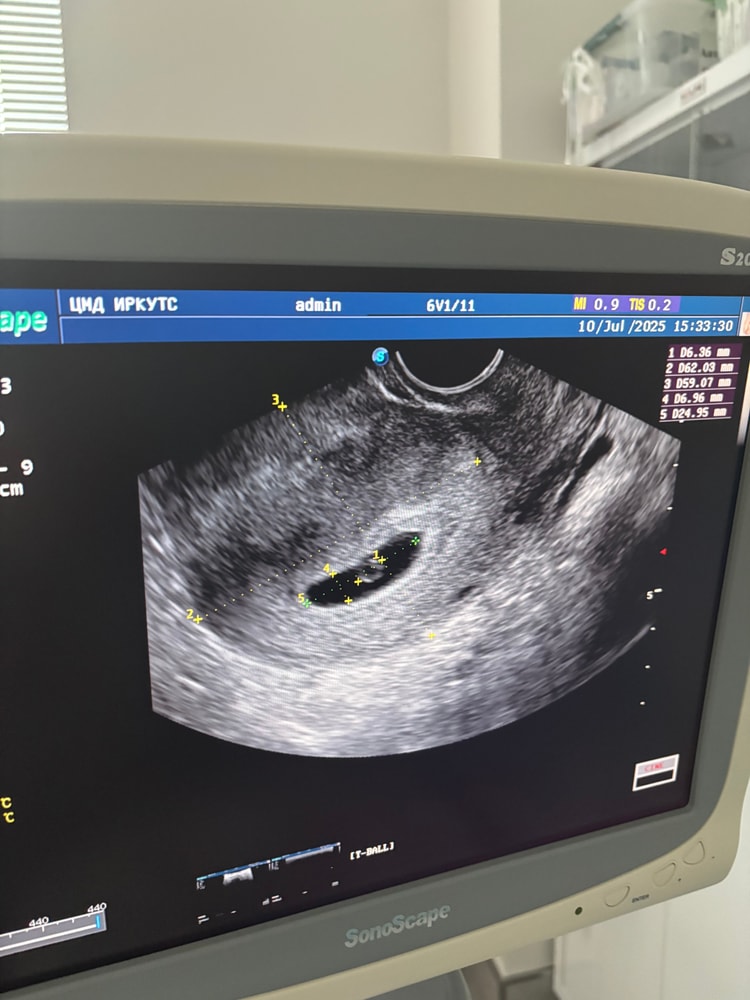

Переделайте УЗИ,глянула ваши записи у вас 29 дпо и эмбрион 7 мм какой-то большой, наверное ошиблись в замерах,при ктр 7 если нет сб,то ставят замершую,но мне кажется у вас не может быть такой ктр на 29 дпо и он меньше намного, поэтому и не услышали сб,у меня на 31 дпо был ктр 5 мм,на 29 дпо если б пошла был бы 3 мм максимум и не факт что услышали бы,я думаю не все потеряно

Ника, не отчаивайтесь,последнее время часто встречаются посты где меряют криво и косо, переделывают и оказывается все хорошо и размеры другие,да и темболие 29 дпо это не тот срок чтобы ставить зб,а вот ктр 7 мм на такое дпо меня смущает,он тянет на 35 дпо, поэтому думаю что ошиблись и все появиться

Мечтательница

За Пя не переживайте, у вас нормальной формы, у меня такое же было. Потом все выровняется.

Пя нормальной формы, но сб уже должно быть. До 5 мм ктр еще допустимо без сб, потом должно быть. Переделайте через пару дней, вдруг чудо случится.